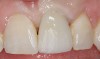

Achieving outstanding esthetics with implant dentistry is a reality (Figure 11 and Figure 12). Restorative efforts require disciplined steps to attain predictable results. To paraphrase my mentor, Cary Shapoff, DDS, renowned for his knowledge of periodontal disease treatment, bone grafting procedures, and dental implant surgery, implant esthetics is a series of well-planned, well-executed small steps that add up to a successfully restored fixture.